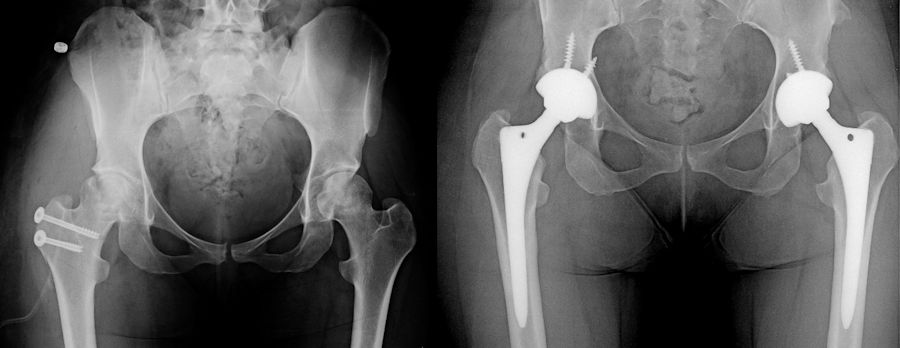

Femur başında çökme meydana geldikten sonra kalça eklemini koruyan cerrahilerin başarı oranları bariz olarak azalır. Mikrocerrahi ile damarlı kemik nakilleri, ölü kemik bölgesini yük taşıyan bölgeden uzaklaştıran osteotomi ameliyatları ya da femur başındaki ölü kemiği tamamen kazıyıp, vücudun başka yerinden alınan canlı kemik dokusu ile doldurulduğu ampül (lightbulb) ameliyatları protez için yaşı çok genç olan hastalarda uygulanabilir. Bu cerrahilerin başarı oranları çok yüksek değildir, protezin bir süre ertelenmesi için uygulanabilirler.

Kalça eklem koruyucu cerrahilerin çökmeyi engelleyemediği veya hastalığın çok ilerlediği aşamada başvuran hastalarda, bir süre ağrı kesiciler ve aktivite sınırlaması ile takip yapılabilir. Başın şeklinin bozulduğu, ileri kıkırdak hasarı ve şiddetli yakınmaları olan hastalarda seçkin tedavi total kalça protezidir. Ağrıyı tamamen geçirme ve kalça hareketlerinin kazanılmasında protezden daha üstün bir tedavi yoktur. Buna karşın kalça protezi üst düzeyde darbeli sporlara izin vermez, yıllar içinde aşınma/gevşeme, %1 civarında enfeksiyon ve % 2 civarında çıkık riskine sahiptir. Özellikle genç hastalarda, protezin ömrünü uzatan ve çıkık riskini en aza indiren robotik cerrahi yöntemleri tercih edilmelidir.